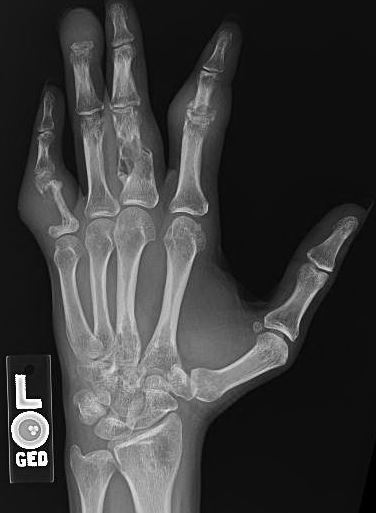

Case Presentation: A 29-year-old African American male with no prior past medical history initially presented to the Orthopedics clinic for evaluation of multiple soft tissues masses. They had been present over all four extremities as well as the back and had been progressively increasing in number. Due to pruritis patient would scratch them and they would bleed and then scab over. Also had bony pain in numerous locations including his left hand, right knee and bilateral wrists. He complained of a 6 month history of blurry vision and also endorsed 15 pounds of unintentional weight loss over last few months. No reported fevers, trauma, foreign travel. A left forearm mass was biopsied and revealed non caseating granulomatous inflammation with no neoplastic changes but did reveal yeast on the smear. Patient was referred to hospital for concerns for systemic fungal process. On examination patient had multiple 2-3 cm soft tissues masses over all the extremities with some having ulcerations or scabs. There was bilateral small cervical lymph nodes palpated along with axillary and inguinal lymphadenopathy. Ophthalmological exam revealed exposure keratitis and iritis. Initial labs showed only mild normocytic anemia. X-rays of bilateral forearms were obtained and revealed multiple bony lytic lesions in both upper extremities. Neuroimaging showed multifocal bihemispheric cervical cord, intra-orbital and intrasinus lesions along with infiltrative masses in bilateral lacrimal glands. CT chest showed mediastinal, perihilar, and bilateral axillary adenopathy. ACE levels were checked and were elevated. Given the constellation of clinical symptomatology and results of imaging studies along with pathology the diagnosis of disseminated sarcoidosis was established. Therapy was initiated with intravenous steroids and discharged on high dose oral steroids and topical ocular steroids with outpatient close follow up.